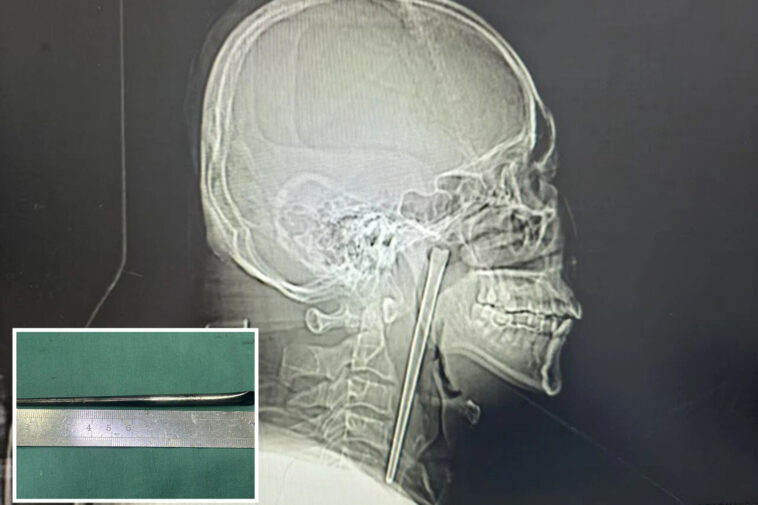

A drunk man in China swallowed a metal chopstick while eating dinner eight years ago — and decided to leave it lodged in his throat until a surgeon finally yanked it out last month, according to a jaw-dropping report.

The “alcoholic” patient, identified only as Mr. Wang, went in for a check-up shortly after gulping down the five-inch utensil in 2018 but refused to have it removed, according to a hospital case study published in March.

Wang, 46, didn’t want doctors to cut his neck open at the time, so he lived with the oddity — and discomfort for years, the South China Morning Post reported.

Surgeons performed a minimally invasive operation to remove the obstructive object via Wang’s mouth instead of slicing open his neck, according to the hospital’s report.

His vocal cords and nearby mucous membrane were luckily not injured and functioned normally after the surgery, according to the report.